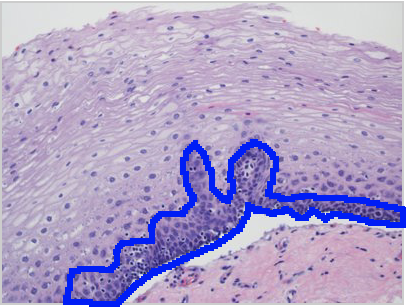

In this image, identify the layer of cells that are involved in renewal of mature epithelial cells!

Epithelial tissues are relatively labile structures whose cells are renewed continuously by mitotic activity and stem cell populations. The rate of renewal varies widely; it can be fast in tissues such as the intestinal epithelium, which is replaced every week. In stratified epithelial tissue such this squamous epithelium of the esophagus, stem cells and mitosis occur only within the basal layer in conact with the basal lamina.